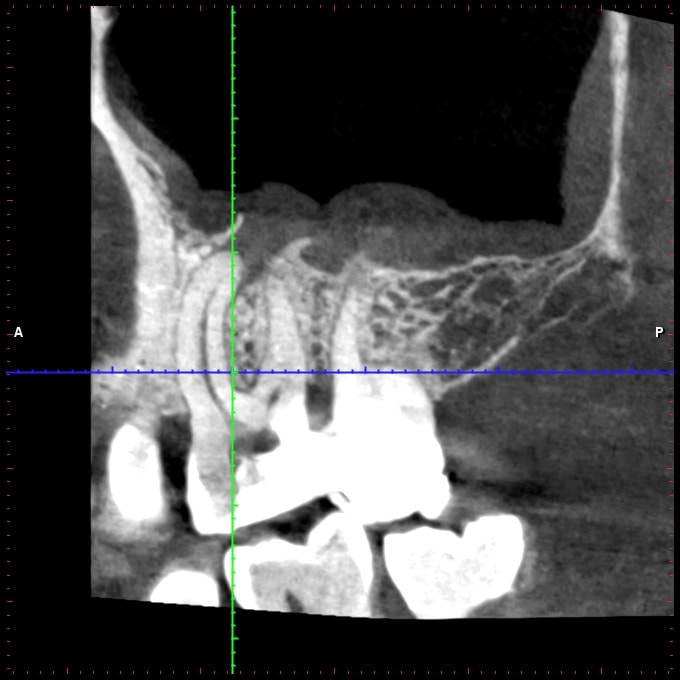

J'ai ce matin un patient qui se présente pour une fracture de 16, asymptomatique.

Test froid négatif, la dent présente une PDP qui radiologiquement ressemble à de la biodentine, cliniquement parait plus blanc.

Je fait une cbct: 4 canaux, lésion infectieuse sur chaque racine et surtout, ce qui ressemble à une résorption interne de la racine palatine.